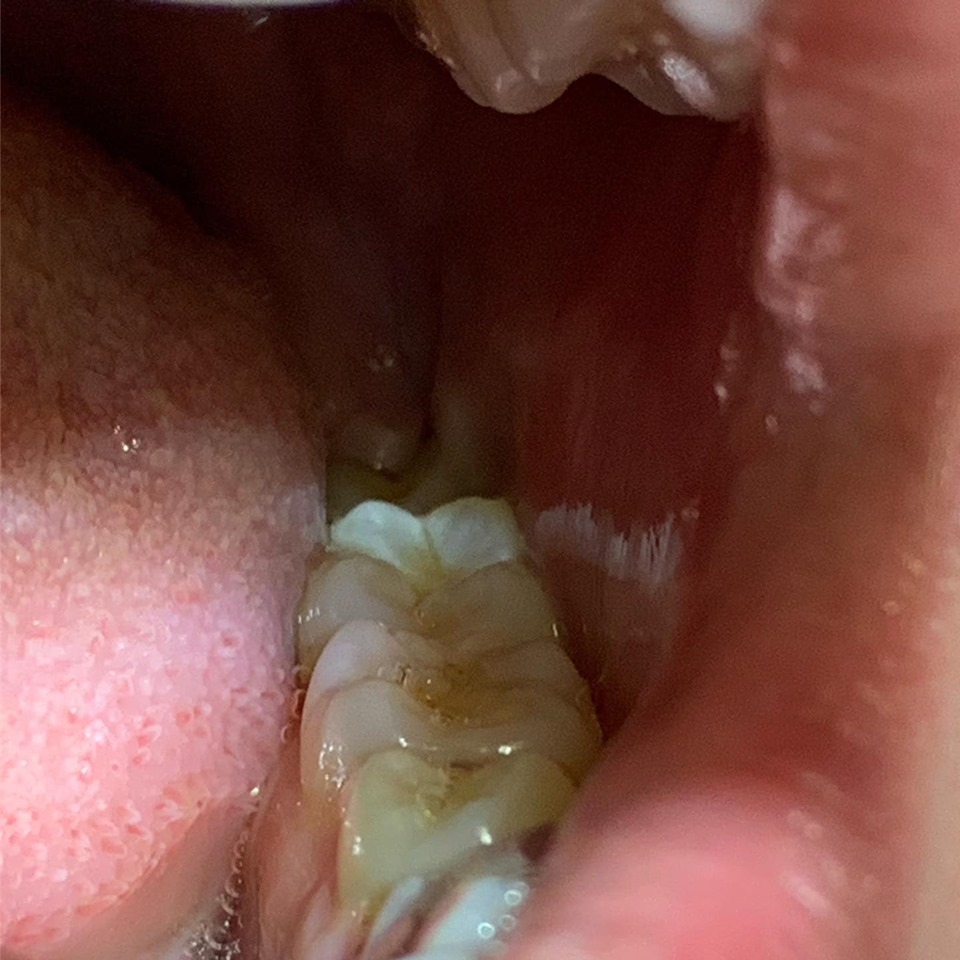

✔️Θεραπευτική προσέγγιση: Εξαγωγή ημιέγκλειστου φρονιμήτη. ✅ Χρόνος εξαγωγής: 30 λεπτά

❓ Επιπλοκές: Πιθανό μικρό οίδημα στην περιοχή, ελάχιστος μετεγχειρητικός πόνος